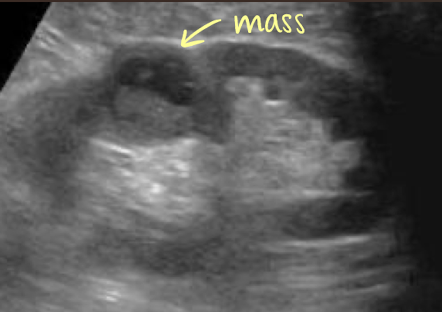

renal cell carcinoma (RCC)

MC renal malignant

higher incidence in men ~60-70 years old

s/s: hematuria, flank pain, and palpable mass

associated with von Hippel Lindau disease, acquired cystic disease in dialysis patients, and tuberous sclerosis

metastasis to lungs, mediastinum, liver, bone, ipsilateral kidney

what are other names for RCC?

hypernephroma and Grawitz Tumor

SONO: renal cell carcinoma (RCC)

isoechoic or hyperechoic

solid or cystic

intratumoral calcification

hypoechoic rim (represents vascular pseudocapsule on color Doppler)

MC vascular patterns is “basket sign” and/or “vessels within tumor”

?invasion of the renal vein and IVC

RCC can invade what vessels?

renal vein and IVC

?? describe

RCC

“isoechoic solid circumscribed structure noted in MP/LP of RK measuring 3 cm x 3 cm x 3 cm. difficult to determine border”